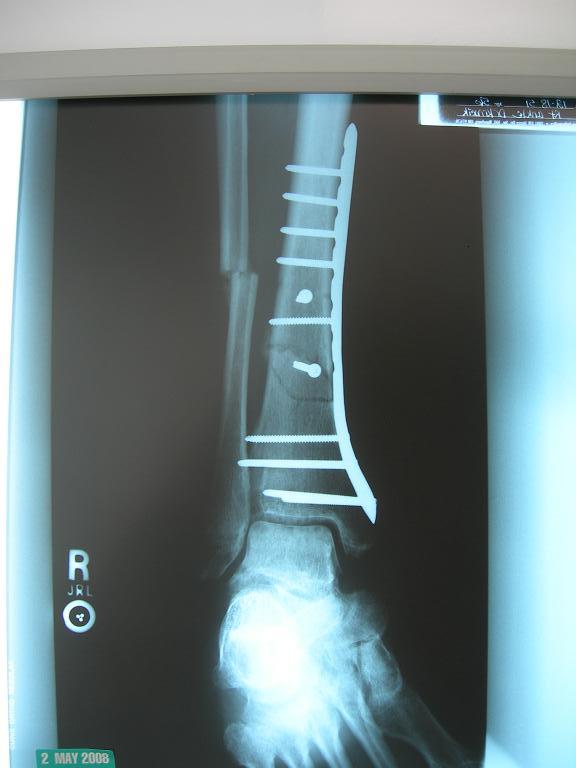

here's what it looked like after,, $60k

went in yesterday

now walking on it

with lots of swelling.

watch out for slednecks

DSCN2342.JPG |

| Damn blowhard, that's a lot of metal!

That's whut I said, G-Man

but he seemed happy with it

"about 50% connected" he said

only 5% of my weight is on the fibula